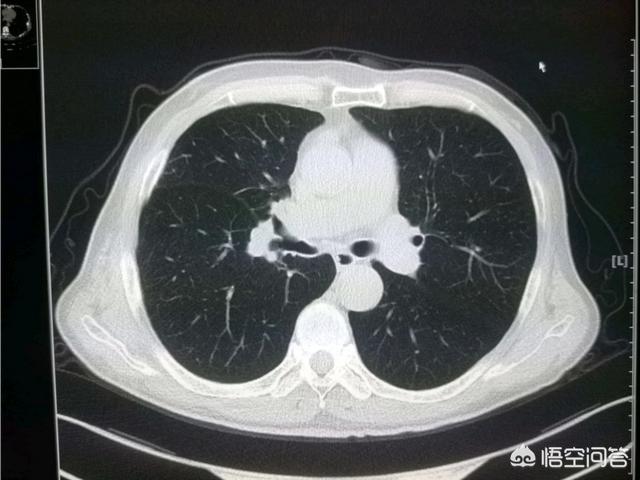

上图就是一位比较早期的食管癌病人。手术成功切除食管中下段。把食管上段和胃吻合。已经八年半了。恢复得很好。

这是一位73岁的大细胞癌。肿瘤9厘米。手术做了好几个小时。成功切除!